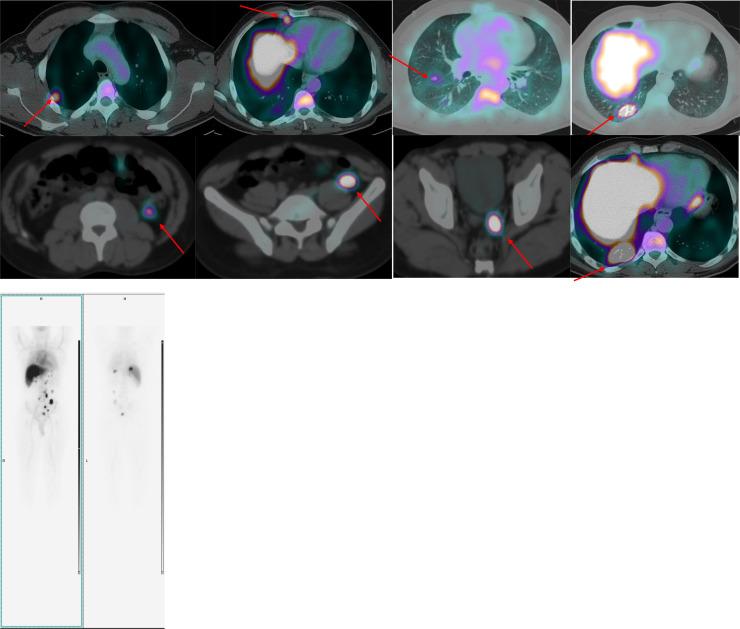

A 37-year-old male patient presented complaining of right flank pain. As an incidental finding on CT, the spleen was not visualized and there were multiple rounded peritoneal tissue nodules, radiologically pattern is mostly suggestive of splenosis. Lung bases showed 2 right lower lung lobe nodules. A dedicated chest CT scan revealed few other pulmonary and pleural nodules. A 99mTc heat damaged denatured red blood cells SPECT CT scan was performed, which revealed right thoracic splenosis, a rare entity to be seen at that location.

https://cdn.ncbi.nlm.nih.gov/pmc/blobs/7876/12512990/86af00a13e83/gr1.jpg